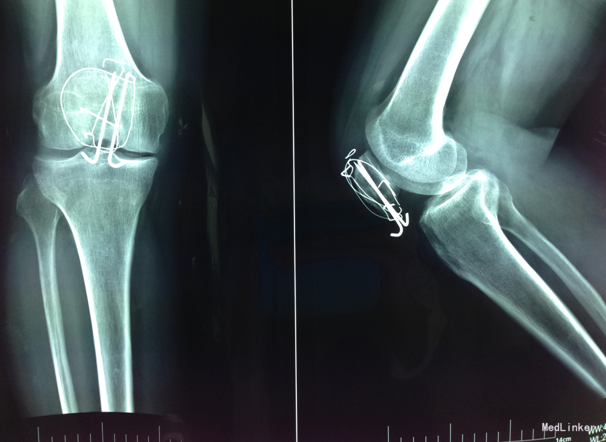

术后复查X线片示骨折复位良好,内固定在位且牢靠。根据骨伤科三期辨证理论,早期因瘀血停滞影响骨 痂生长,故以活血化瘀,消肿止痛为主,应用桃红四物汤。术后证属肝肾亏虚,气血不足,治以补益肝 肾,补气养血,应用愈骨胶囊等药物促进骨折愈合。术后嘱患者继续石膏托外固定,注意陪护,3月内扶 双拐、按指导患肢不负重功能锻炼;休息3个月,加强营养,促进骨折愈合;继续中药应用,促进骨折愈 合;定期复查,(1月、3月、6月);不适随诊。 本病例中医药应用结合手术复位,早期将骨折复位, 中医药早期应用活血化瘀、消肿止痛,可迅速缓解患者症状。中医药中后期应用可促进骨折愈合,加快 术后恢复,可使患者获得满意的术后疗效。